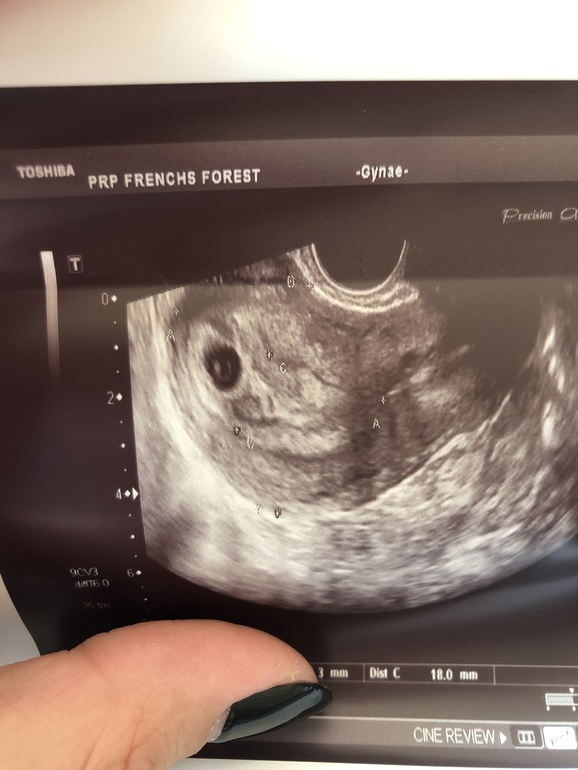

А это результат УЗИ с сыном нед. в 7 по-моему. Прям чётко видно ЖМ и эмбрион в углу)))

Да,написала что эмбрион 2 мм. И желточный 3 мм. Но я эмбриона здесь не вижу

На узи я видела,то же что и на фото здесь)) именно это что более белое,она посчитала за эмбрион.